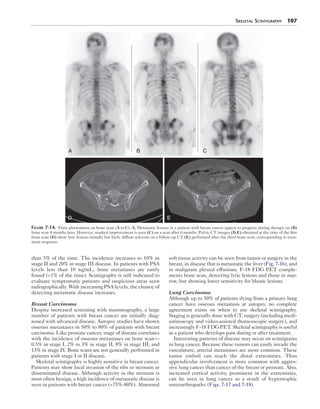

A B C

D E

Figure 7-14. Flare phenomena on bone scan (A to C). A, Metastatic lesions in a patient with breast cancer appear to progress during therapy on (B)

bone scan 4 months later. However, marked improvement is seen (C) on a scan after 6 months. Pelvic CT images (D,E) obtained at the time of the first

bone scan (D) show lytic lesions initially but fairly diffuse sclerosis on a follow-up CT (E) performed after the third bone scan, corresponding to treat-ment

than 5% of the time. The incidence increases to 10% in

stage II and 20% in stage III disease. In patients with PSA

levels less than 10 ng/mL, bone metastases are rarely

found (<1% of the time). Scintigraphy is still indicated to

evaluate symptomatic patients and suspicious areas seen

radiographically. With increasing PSA levels, the chance of

detecting metastatic disease increases.

response.